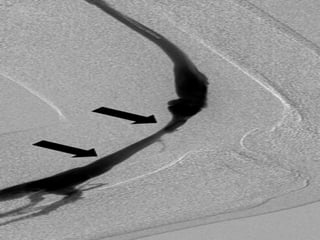

Major veins of the arm

Major veins ofthe arm • Dorsal • Cephalic • Basilic • Cubital Fossa